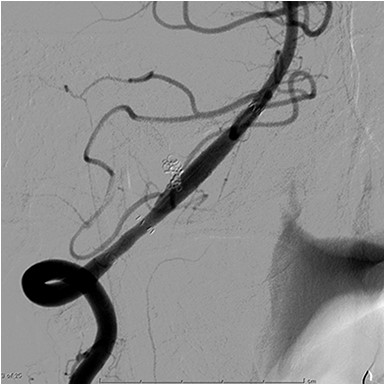

A 48-year-old man was admitted to our hospital because of loss of consciousness after a sudden nuchal pain. Brain computed tomography (CT) showed diffuse SAH (Fig. 1A). The following CT angiogram showed a fusiform aneurysm at the right vertebral artery with contralateral hypoplasia (Fig. 1B). The endovascular procedure was performed under general anesthesia. The patient received a loading dose of 200 mg of aspirin and 300 mg of clopidogrel via a nasogastric tube. A preoperative angiogram showed VAD with a blister at the pseudolumen (Fig. 2A). Initially, a stent (Enterprise, 4.5 mm × 37 mm; Codman, Raynham, MA, USA) was deployed from the basilar artery to the right vertebral artery. A second stent (Enterprise2, 4.0 mm × 30 mm) then overlapped the first stent, covering the pseudolumen (Fig. 2B). Coiling was performed from a microcatheter (Excelsior SL-10/45; Boston Scientific, Fremont, CA, USA), which was jailed in the pseudolumen. After the first coil perforated the blister, a balloon catheter (Scepter C, 4.0 mm × 15 mm; Microvention, Tustin, CA, USA), which was exchanged with a stent delivery catheter, was inflated in the stent. All five small platinum coils (Target nano, 2 mm × 4 cm and 1.5 mm × 2 cm; Stryker, Fremont, CA, USA) completely occluded the pseudolumen (Fig. 2C), and the right vertebral artery was preserved (Fig. 2D). Magnetic resonance imaging, which was obtained 3 weeks after the procedure, showed right cerebellar infarction without damage of the brainstem (Fig. 3). The patient recovered and returned to his former job after 2 weeks of intensive care and 3 months of rehabilitation therapy. An angiogram, which was obtained 6 months after procedure, showed no recurrence of VAD (Fig. 4).

(A) Preoperative angiogram shows a dissecting aneurysm with a blister. (B) The first stent was deployed across the aneurysm and the second stent overlapped the first stent. (C) Coiling was performed under the support of a balloon catheter after the first coil perforated the blister. (D) Complete obliteration of the pseudolumen was achieved and the parent artery was preserved.